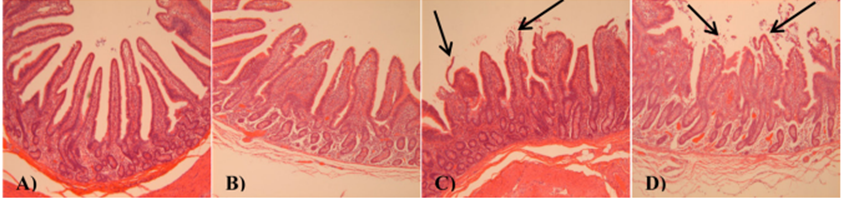

Imagen tomada de Pearce et al., en 2014: Cambios temporales en la morfología del íleon por estrés térmico (EC; 37°C y aproximadamente 40% de humedad). A) 0 h de exposición a EC, B) 2 h de EC, C) 4 h de EC y D) 6 h de exposición a EC. Obsérvese el acortamiento de la longitud de las vellosidades y el aumento de la autólisis de las puntas de las vellosidades a medida que aumenta la duración de la exposición al estrés por calor se intensifica. Las flechas negras indican áreas de autólisis. El tratamiento EC de hora cero representa condiciones térmicamente neutras (21 °C y aproximadamente 70 % de humedad).

Una de las características de los animales bajo estrés por calor es la activación de un mecanismo fisiológico para aumentar la perdida de calor endógeno, provocando un desvío en el flujo sanguíneo hacia la periferia, esta alteración reduce el flujo sanguíneo y el aporte de nutrientes al tracto gastrointestinal, lo que provoca hipoxia local, producción de radicales libres y deterioro de la estructura intestinal. Como consecuencia de esto el epitelio intestinal sufre un aumento de la permeabilidad, incrementando el paso hacia circulación general de toxinas endógenas y exógenas, como resultado se pueden originar respuestas inflamatorias tanto locales como sistémicas (SIRS) y activación del sistema inmunitario del animal generando de esta manera una redistribución de los nutrientes que originalmente estarían destinados a producción (Ross et al., 2017, Gabler et al., 2018, Mayorga et al., 2020, Liu et al., 2022). Solo la exposición por tres días a estrés por calor diurno aumenta un 150% las endotoxinas séricas (Gabler et al., 2018).